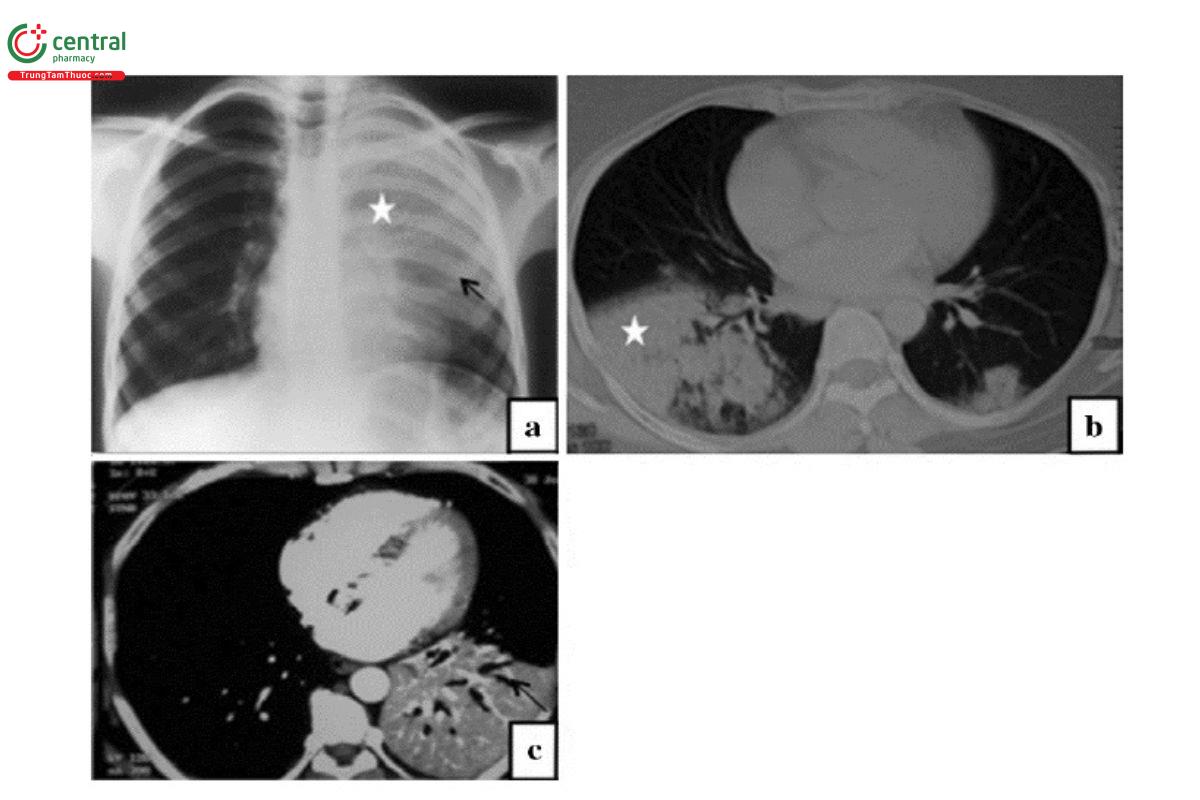

Viêm phổi do Streptococcus pneumoniae: Hình ảnh tổn thương là viêm phổi phế nang/thùy, thường có hình ảnh phế quản hơi, không thay đổi kích thước vùng phổi đông đặc và không có hang. Thùy dưới thường gặp nhiều hơn và có thể xuất hiện ở nhiều thùy. Tổn thương hai bên gặp ở khoảng một nửa số bệnh nhân.

Chú thích: a) Hình ảnh đông đặc (dấu sao) ở thùy trên bên trái với dấu hiệu phế quản hơi (mũi tên đen). b) Hình ảnh đông đặc thùy dưới bên phải (dấu sao) trên CT. c) Hình ảnh đông đặc thùy và dấu hiệu phế quản hơi (mũi tên đen).